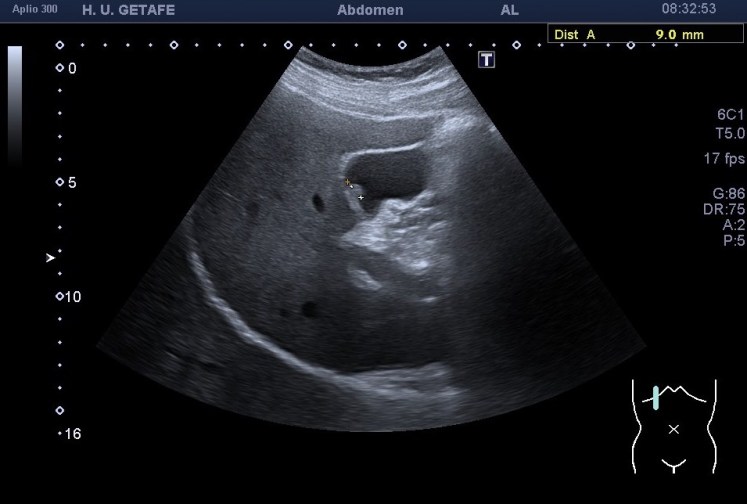

283. Pólipo vesicular. Zoom.

Son estructuras redondeadas pegadas a la pared vesicular hiperecogénicas. Normalmente única, pueden aparecer en número variable lo que se conoce como una poliposis vesicular

No presentan sombra posterior.

No se mueven al cambiar de posición al paciente.

El estudio del pólipo tras su localización se realiza en dos proyecciones, variando al paciente de posición para ver si se mueve. Ponemos doppler, tanto color como modo angio, con el objetivo de demostrar un vaso en el interior del pólipo, que lo delataría como una estructura de aspecto maligno y debería ser valorado por el radiólogo y por el cirujano convenientemente. Por eso ajustar el doppler es muy importante en este caso también.

Medimos para hacer seguimiento de la lesión si se requiriese así. Aplicamos zoom para estudiarlo detalladamente, a mi me encantan las imágenes en este Canon. El Zoom es muy bueno y el estudio del pólipo gana muchísimo. Hablando del Zoom…

Como muy bien puedes observar el caso es bastante anodino, las imágenes te las he puesto y son la excusa para explicarte el uso del Zoom. Habitualmente es un ajuste ecográfico que no usamos en exceso, solo puntualmente, puede pixelar en exceso la imagen, como cuando hacemos una foto con nuestro móvil y la ampliamos con el gesto de nuestros dedos…pixelamos la imagen, perdemos resolución, pero lo nuevos equipos, ganan en esto también y con las sondas de baja frecuencia podemos conseguir imágenes muy bonitas de alguna ecoestructura pequeña y que nos interese medir bien, y este caso me resultó muy plástico y te lo quería explicar. Repasamos el concepto de pólipo vesicular y lo enlazamos con el uso del zoom.